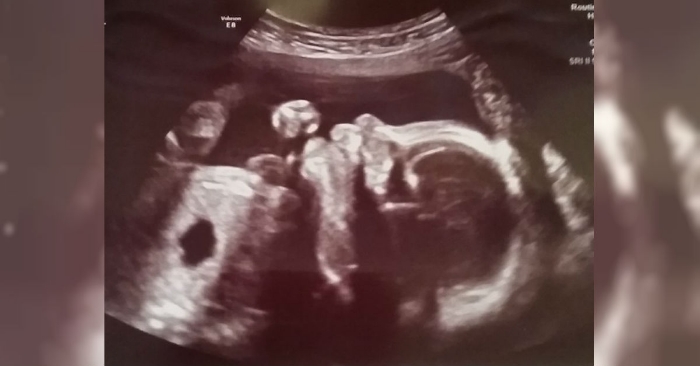

Daljinder bor sammen med ektemannen Mohinder, som er 79 år gammel. De har vært gift i 47 år, og hadde levd som pensjonister i en god stund før de ble foreldre. De siste to årene hadde paret gjennomgått IVF-behandling (også kjent som in vitro-fertilisering). Det ga til slutt resultater, og Daljinder ble gravid.